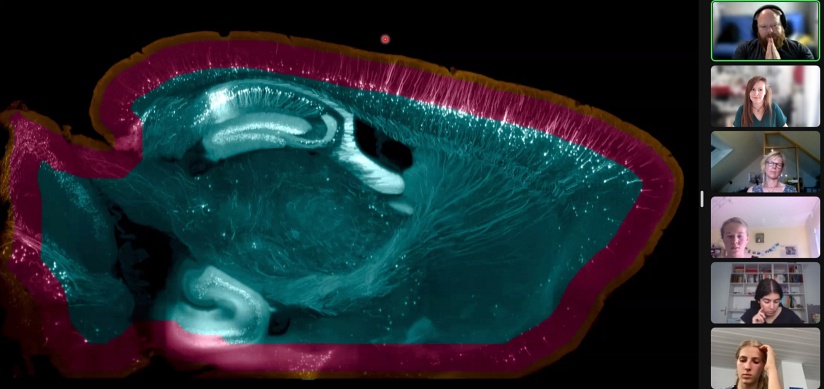

29.06.2022: Florian Vollrath: 2P light-sheet microscopy for fast whole-brain imaging

- Die Weiterentwicklung eines 2 Photonen light-sheet Mikroskops trägt zur Optimierung der Auflösung bei.

- Erläuterung der Methode des „optischen clearings“, bei dem Proben durchsichtig gemacht werden.

- Das Objekt kann dank dieser Methoden 15 mm (statt der bisherigen 0,00015mm) durchleuchtet werden.

- Bilder mit enormer Schärfentiefe werden erzielt.

- Faszinierende Aufnahmen verschiedener Ebenen des Gehirns entstehen!

Bild copyright: MPI for Brain Research